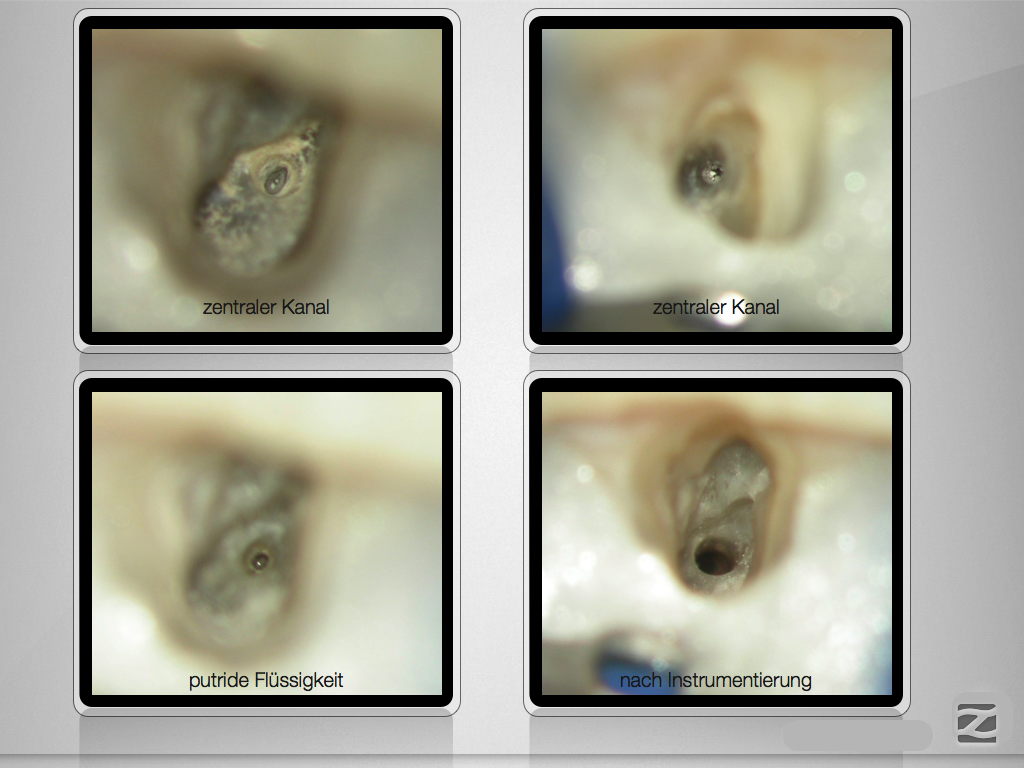

Folgen eines Milchzahntraumas (3)